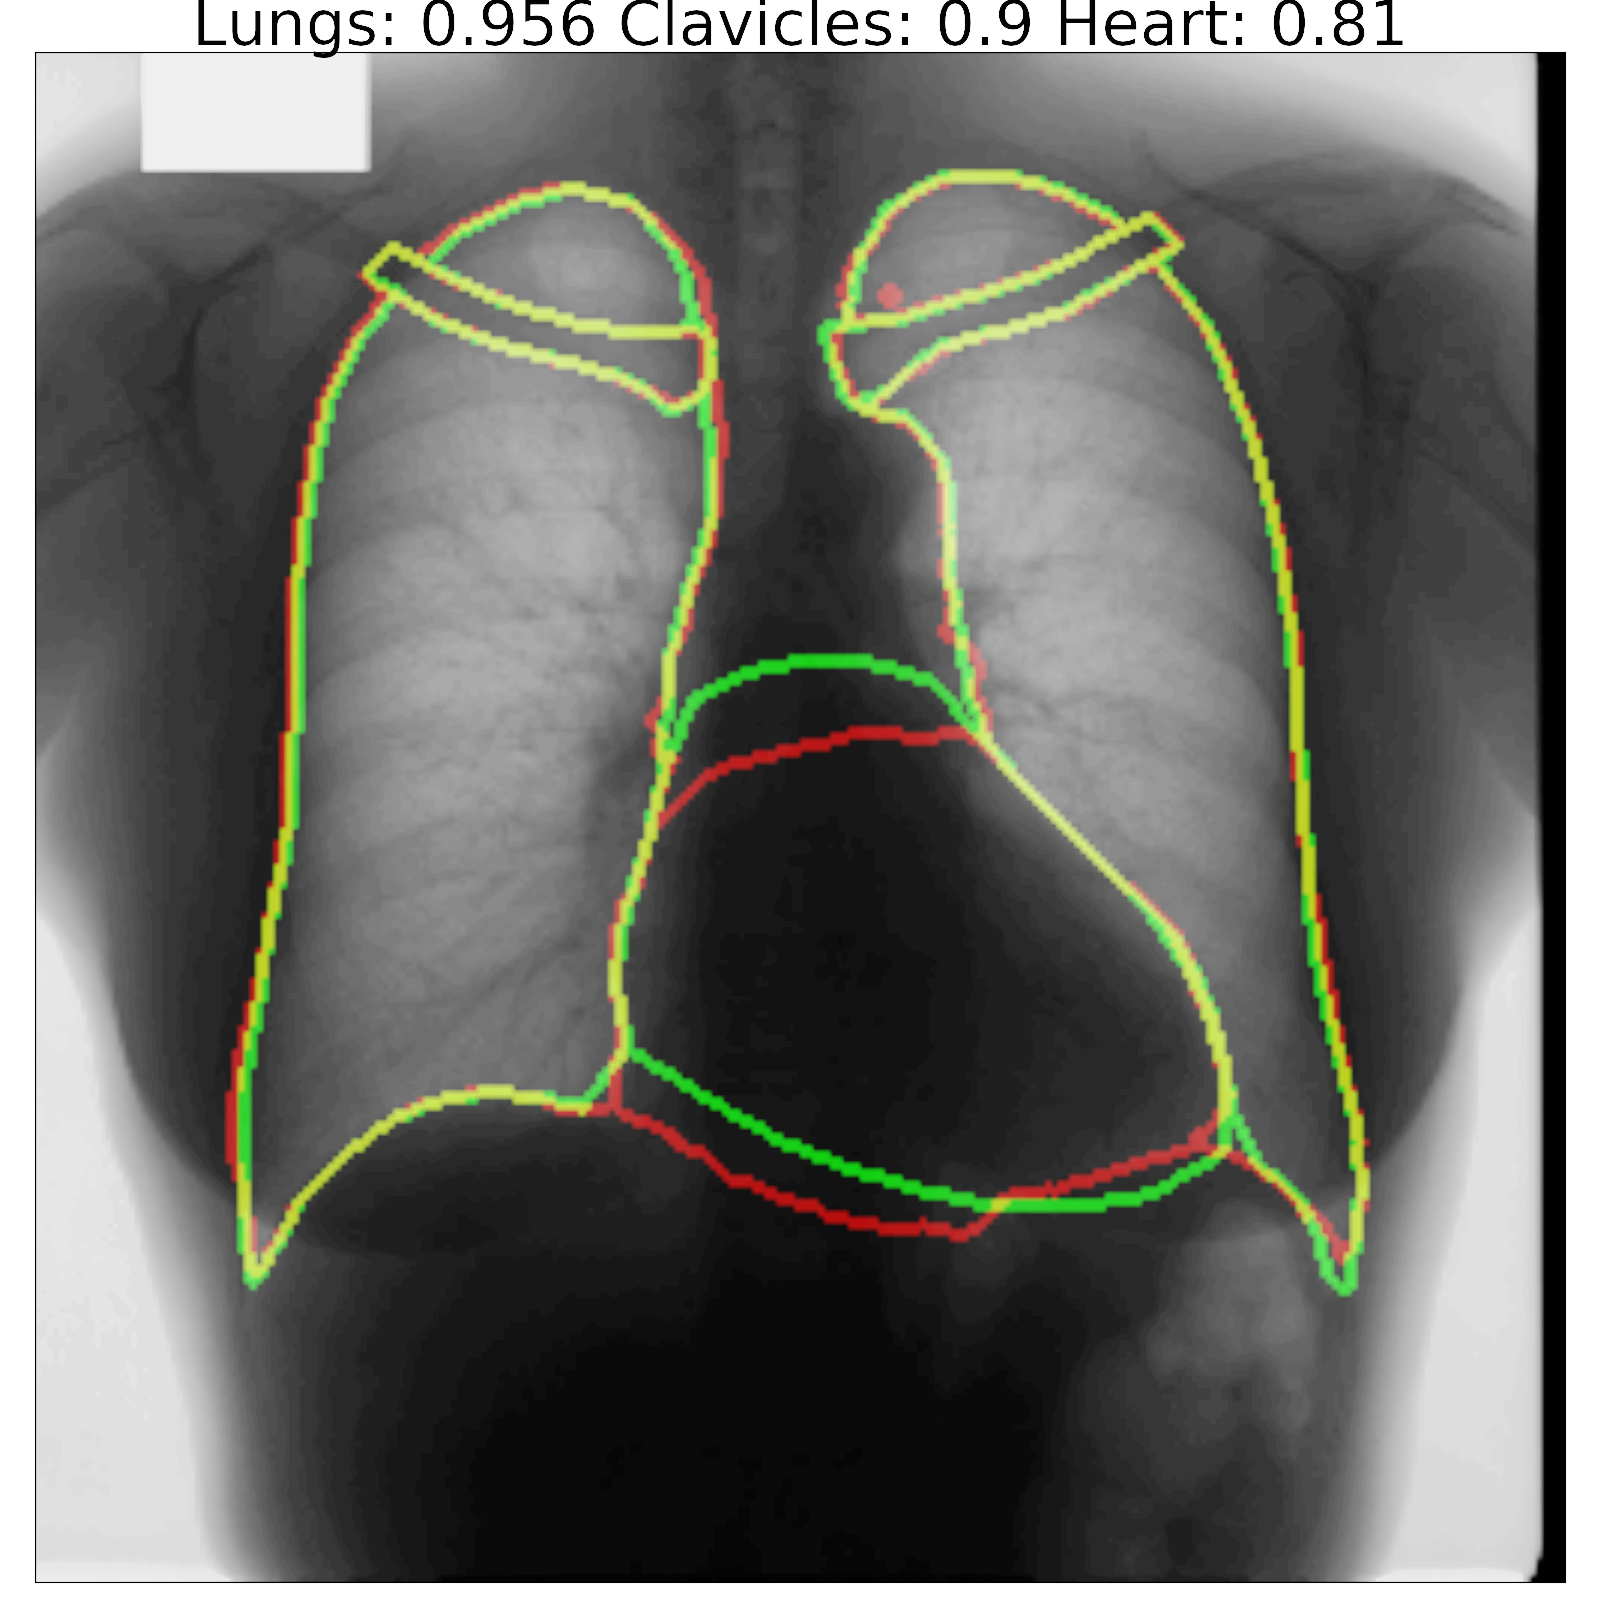

Figure 7: Segmentation results and corresponding Jaccard scores on some images for U-Net (top row) and proposed InvertedNet with ELUs (bottom row). The contour of the ground-truth is shown in green, segmentation result of the algorithm in red and overlap of two contours in yellow.

Fig. 7 shows a few examples of the algorithm results for both successful and failed cases for U-Net (top) and the InvertedNet  trained with the ELU and loss function based on the Dice coefficient. The white boxes show Jaccard scores for lungs, clavicles and heart. To extract the shape contours of the segmentation and ground-truth, we used a morphological outline extraction algorithm on both segmentation result and reference masks. The contour of the ground-truth is shown in green, the segmentation result of the algorithm in red and the overlap of two contours in yellow colors.